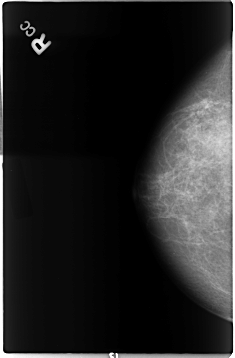

B_3038_1.RIGHT_CC

RIGHT_CC LINES 4648 PIXELS_PER_LINE 3048 BITS_PER_PIXEL 12 RESOLUTION 50 NON_OVERLAY